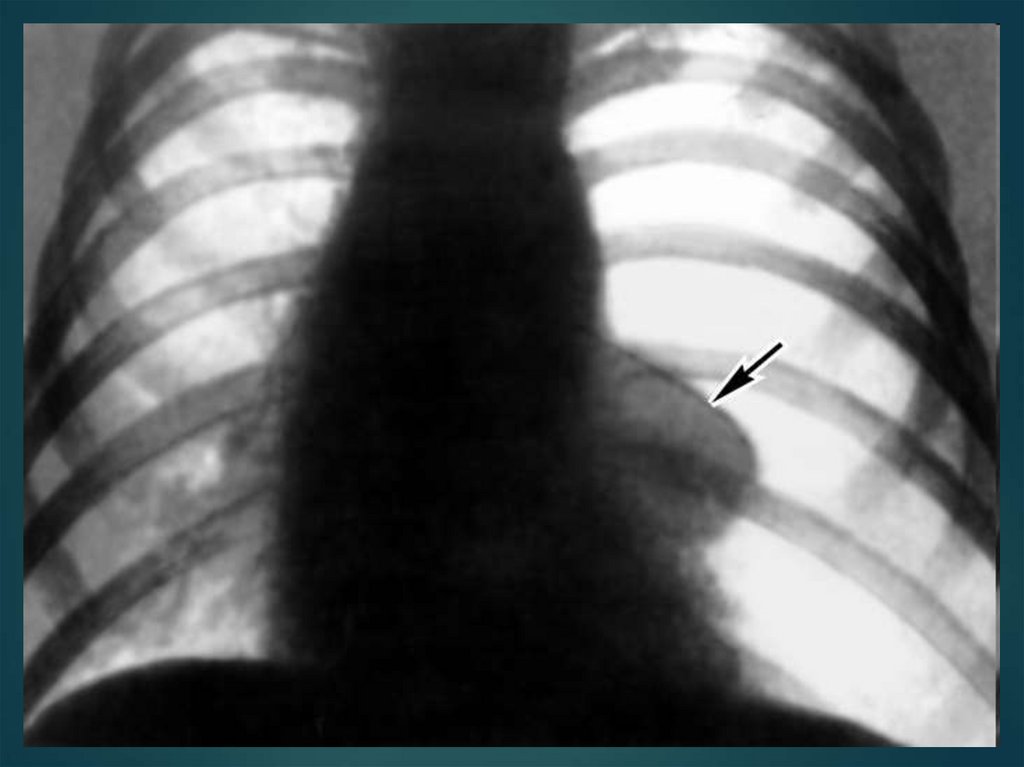

48. Закрытый пневмоторакс

возникает в результате быстрого

Состояние средней тяжести, бледность кожных

покровов, одышка. При аускультации ослабление

дыхания на стороне поражения. При перкуссии –

коробочный звук в верхних отделах грудной клетки

49. Закрытый пневмоторакс

Небольшое количество воздуха (300—500 см3)

рассасывается в течение 2—3 нед. Если легкое

поджато более чем на 1/4 своего объема,

производят плевральную пункцию для

максимального удаления воздуха.